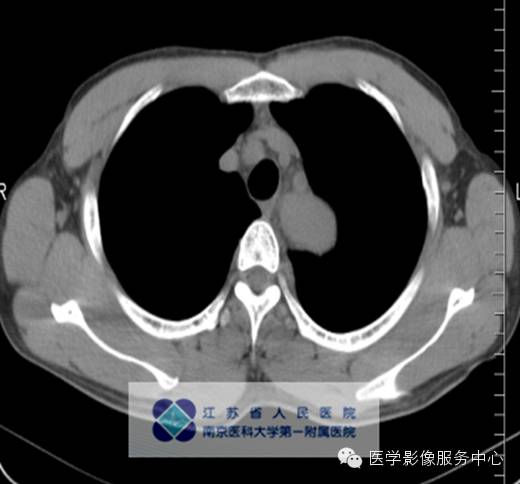

男,27岁,因“查体发现纵隔占位三月余”入院。

影像分析:左上、后纵隔内见类圆形软组织密度增高影,密度尚均匀,边缘清晰,增强扫描均匀强化。

单中心型:大部分为透明血管型,表现为纵隔及肺门圆形或卵圆形较大软组织肿块,边缘光滑锐利可有分叶,多数密度均匀可伴斑点状、树枝状等不同表现钙化。Meador等报道病变强化与病灶大小有关,小于5cm多为均匀强化,大于5cm的多不均匀强化,另外,还与病变的组织学特点如变性、坏死、纤维化的程度有关。